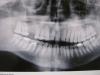

Дмитрий Денисов Опубликовано 19 июня, 2011 Поделиться Опубликовано 19 июня, 2011 Мне 31 год.Не устраивает внешний вид зубов.Особенно на верхней челюсти.(Паталогический прикус,паталогическая стираемость эмали-просвечивает дентин,щели между зубами,несоответствие центральной линии на верхней и нижней челюстях)Какие варианты возможны в моём случае?возможно ли удаление всех 15 зубов на верхней челюсти и постановка полного сьёмного протеза для корректировки прикуса и восстановления эстетичного внешнего вида?Ношение сьёмного не пугает.Так-же рассматривается вариант с удалением 17 18 26 27 28 (поднятие прикуса) и коронки на 15 14 13 12 11 21 22 23 24 25 внешний вид.фото Ссылка на комментарий